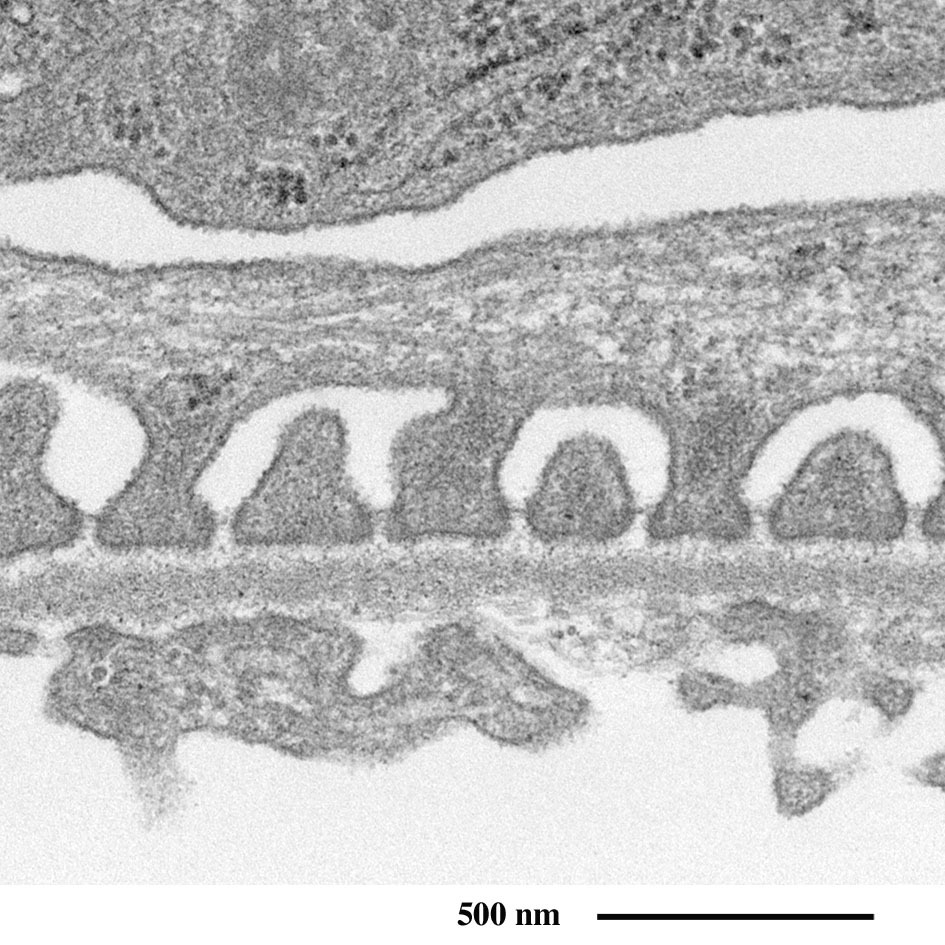

近端小管

为了重吸收原尿中含有的葡萄糖、电解质、水等身体必需物质,

上皮细胞顶端排列着微绒毛以增大表面积。

近端小管上皮细胞